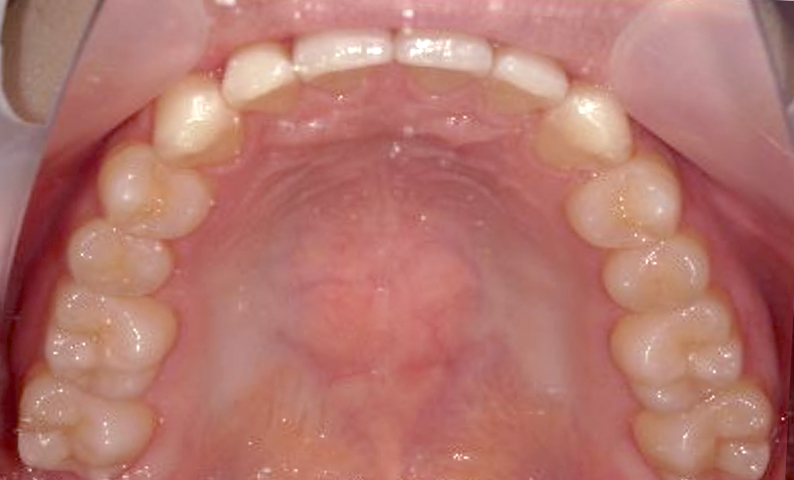

| 治療前 | 治療後 |

|---|---|

|